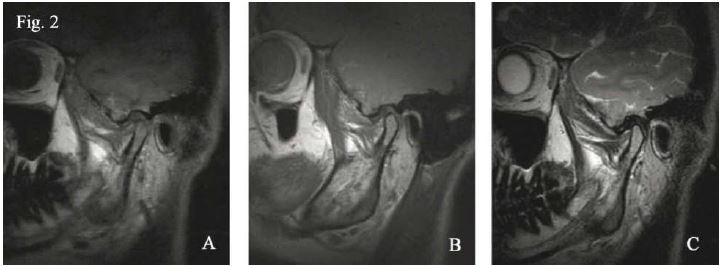

Ampliamente divulgado resulta la aplicación de la RNM para el estudio del disco articular no tan sólo su morfología sino también su dinámica, existiendo así mismo protocolos bien establecidos para ello26,29,30. El disco articular de la ATM está formado por tejido conectivo fibroso, en cortes sagitales de RNM se observa como una estructura bicóncava con una señal homogénea de baja intensidad o hipointensa en su zona anterior, así como la intermedia y la posterior se observa como leve hiperintensidad en condiciones normales o de salud y la zona bilaminar posee una señal intermedia en T1 ponderado.8,26 la porción superior de esta zona bilaminar es rica en fibras elásticas y la inferior en fibras colágenas, ambas separadas por tejido areolar laxo.1 Los tejidos de la zona bilaminar y del músculo pterigoideo lateral presentaran una señal moderada en imágenes T2 ponderadas, mucho más bajas que en T1 ponderada. Se ha demostrado que cortes parasagitales así como paracoronales (figura 2), en T1 ponderado y en difusión protónica ponderada en boca cerrada dan la mejor imagen para evaluar la anatomía de la ATM y no así T2 ponderada28.